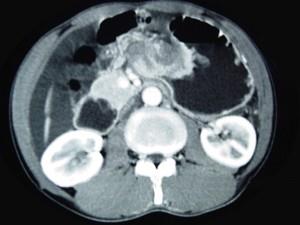

问题 男,65岁,中上腹痛腹胀、消瘦、乏力、纳差,影像检查如图,最可能的诊断是 ( )

选项 A、胃窦癌 B、胃淋巴瘤 C、萎缩性胃炎 D、肥厚性胃炎 E、胃间质瘤

答案 A